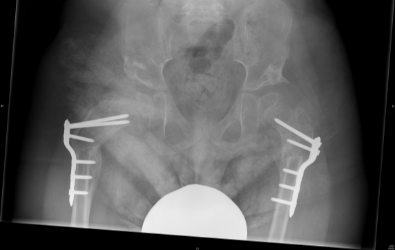

Children with cerebral palsy which are non-walkers need to be screened for hip dislocation. Hip dislocation is common in children with cerebral palsy that are restricted in wheelchairs. Prevention of hip dislocation is important because it causes severe pain, lower limb deformities and scoliosis. In many countries universal pre-symptomatic hip screening is performed which has resulted in significant reduction in the number of hip dislocations. It is therefore recommended that regular clinical and radiological assessment is performed in children with cerebral palsy that are not able to walk. In order to avoid hip dislocation the doctor depending on clinical and radiological assessment in each patient can recommend physiotherapy or orthotic treatment, Botox injections or surgical intervention in order to release soft tissues. However, when hip dislocation results in femoral head uncovering of more than 40%, surgical intervention is required in order to reduce the hip, usually with a femoral and/or a pelvic osteotomy.

The x-rays below are of a child with cerebral palsy (a non-walker) with bilateral hip dislocation and severe pain. The patient underwent bilateral femoral and pelvic osteotomies in order to reduce the hips.

Post-operative